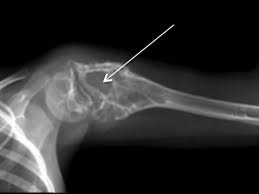

These signs are often easier to see if the tumour is in a leg or arm. One of the most common places for it to go is the hip or pelvis. Pelvis thigh bone (femur) cortical (compact) bone bones of the body bone structure cancer can spread to any bone in the body. This type of pain is usually characterized as burning, itching, or radiating. Symptoms of hip cancer may include: Bone cancer can begin in any bone in the body, but it most commonly affects the pelvis or the long bones in the arms and legs. Bone metastasis may be the first sign that you have cancer, or bone metastasis may occur years after cancer treatment. Rheumatic disease, arthritis or other conditions that affect the tendons surrounding the hip and the hip joint can also cause limping. Metastatic tumors of the bones are usually osteolytic, which means that they dissolve the bone and cause multiple fractures. In fact, noncancerous bone tumors are much more common than cancerous ones. When a bone tumor grows, it presses on healthy bone tissue and can destroy it, which causes the following symptoms: As with other signs of bone cancer, limping can indicate a tumor in the hip. Symptoms of chondrosarcoma and osteosarcoma chondrosarcoma (cancer of the cartilage) and osteosarcoma (cancer of the bone) are cancers that occur most often in the pelvis, as well as the upper leg and shoulder.

Limping if cancer is in a leg; These signs are often easier to see if the tumour is in a leg or arm. The most common symptom of these cancers is bone pain or swelling in the pelvic area. Bone metastasis can occur in any bone but more commonly occurs in the spine, pelvis and thigh. Metastatic cancer can spread to any bone, but it most often spreads to bones in the middle of the body.

Metastatic Bone Disease Orthoinfo Aaos from orthoinfo.aaos.org This gradually progresses to a persistent ache or an ache that comes and goes, which continues at night and when resting. Difficulty moving the arm or the leg with cancer; Bone metastasis can cause pain and broken bones. It can be hard to tell the difference between. A tumour in the chest or pelvis may not be noticed until it grows larger. Bone cancer is rare, making up less than 1 percent of all cancers. Bone cancer can begin in any bone in the body, but it most commonly affects the pelvis or the long bones in the arms and legs. The symptoms of spinal cancer may occur very slowly.